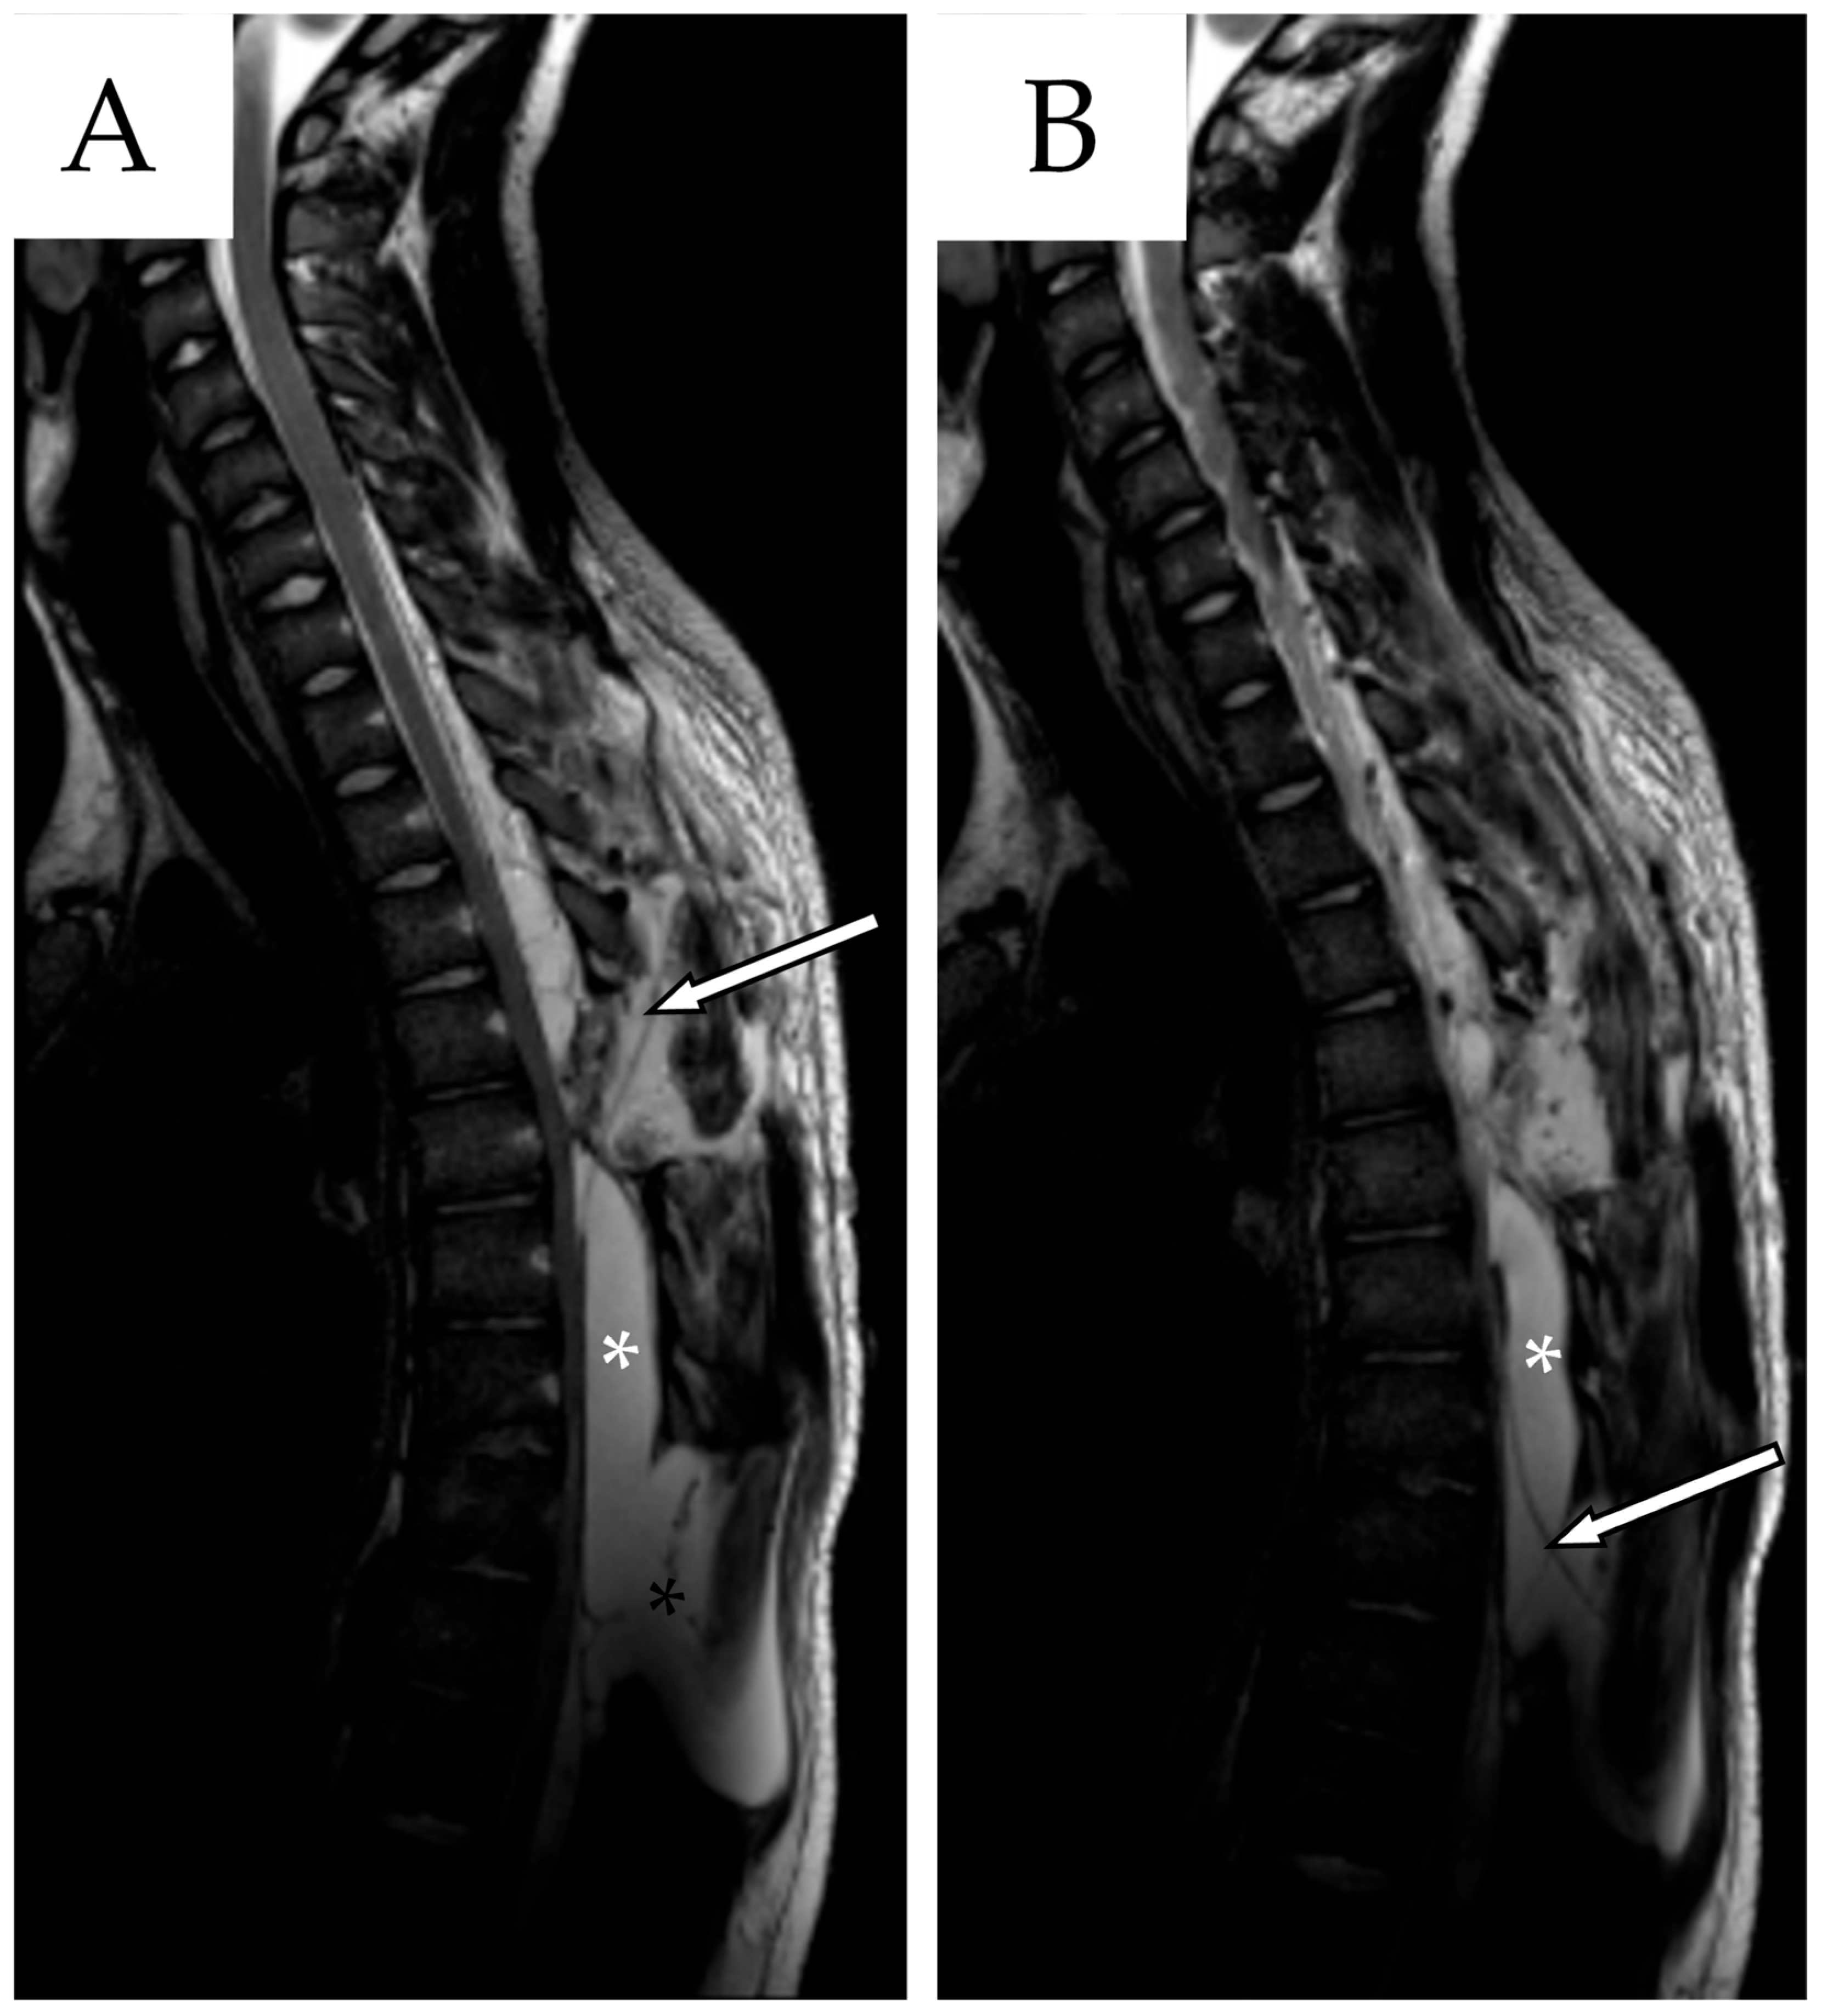

2.2. First Follow-Up

2.3. Second Admission